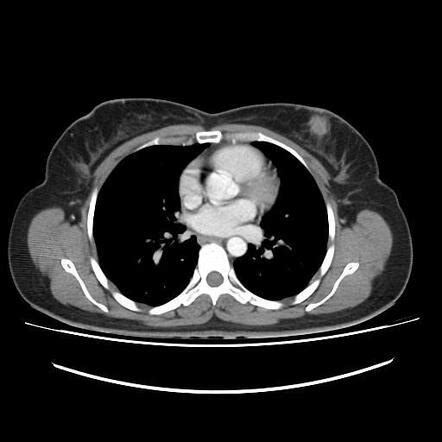

Getting a diagnosis can be a scary time, and understanding the process for diagnosing Triple-Negative Breast Cancer (TNBC) can help ease some of that anxiety. The journey usually starts with you noticing a change in your breast – maybe a lump, skin dimpling, nipple changes, or nipple discharge. If you spot anything unusual, the first step is always to see your doctor . They’ll perform a clinical breast exam and likely order imaging tests. The primary imaging tools are a mammogram and possibly an ultrasound or MRI , depending on your situation and breast density. These tests help visualize any abnormalities. If suspicious areas are found, the next crucial step is a biopsy . This is where a small sample of tissue is taken from the suspicious area, either with a needle or during a minor surgical procedure. The biopsy sample is sent to a lab where a pathologist examines the cells under a microscope. This is where the magic (and the crucial information) happens. The pathologist will determine if the cells are cancerous. If they are, they’ll then perform tests to see what kind of breast cancer it is. For TNBC, these tests are key. They’ll specifically look for the absence of estrogen receptors (ER) , progesterone receptors (PR) , and HER2 protein . If all three are negative, then you’ve got a TNBC diagnosis. It’s important to note that the initial biopsy might be tested for these markers, and sometimes further testing or a repeat biopsy might be needed for confirmation. Once diagnosed as TNBC, the medical team will also want to figure out the stage of the cancer . This involves seeing how large the tumor is and whether it has spread to nearby lymph nodes or other parts of the body. This is usually done through imaging like CT scans, bone scans, or PET scans. Staging is super important because it helps doctors determine the best treatment plan for you. Remember, while a TNBC diagnosis can feel daunting because of the treatment limitations, accurate and timely diagnosis is your best weapon. The medical team is there to guide you through every step, answer your questions, and develop a personalized treatment strategy. Don’t hesitate to ask for clarification on any part of the process; being informed empowers you.